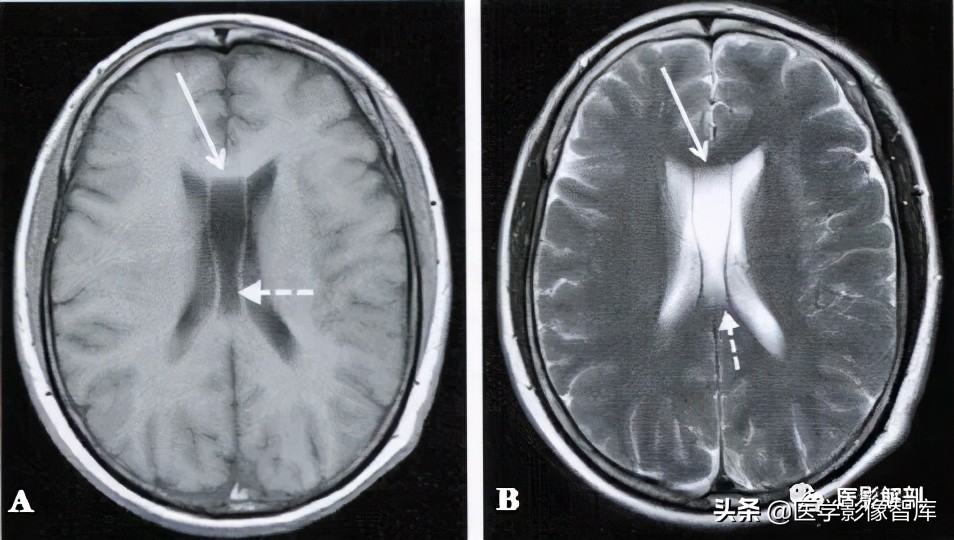

图3 第五、六脑室

男性,40岁。A.轴面T1WI,B.轴面T2WI。在双侧脑室体部之间可见一个条形腔隙,内部充满长T1、长T2信号影,两侧的薄膜将其与侧脑室的脑脊液信号 相隔,腔隙的前部为第五脑室(长箭),后部为第六脑室(虚箭)。

若透明隔侧壁向两侧弯曲甚至膨隆,失去正常的平行状态,且侧壁间的距离≥10mm,则称其为透明隔囊肿(图2)。Vergae腔位于透明隔间腔之后,胼胝体之下,双侧侧脑室体部之间,表现为前窄后宽的纵形腔隙结构,其内为脑脊液信号,并存的Vergae腔与透明隔间腔呈条带状,双侧的腔壁大致平行(图3)。